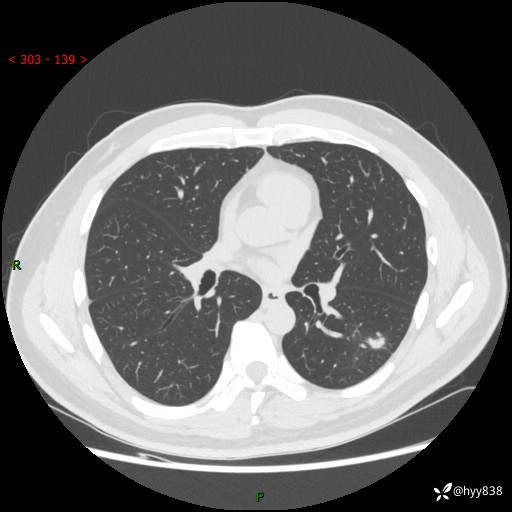

中年男性,胸闷3月余。多发团片、肺小叶分布、空气支气管征、明显强化---结果公布~

现病史:患者3月前出现胸闷,卧位时加重,坐位时缓解,无咽痛、咳嗽,无头痛,无全身酸痛,无结膜充血,无胸痛、心慌,无咯血,无呼吸困难,无咳痰,2024-07-02于当地市第一民医院行胸部CT,结果不详,2024-07-05就诊于我院急诊内科,行胸部CT同时增强,结果示:左肺下叶多发结节灶,考虑感染可能。今患者为求进一步诊治来我院,门诊以“肺部感染”收入我科。 患者本次起病来精神、食欲、睡眠尚可,大小便可,体力,体重无明显变化。

胸部CT平扫+增强

各期CT值:30hu 90hu 77hu